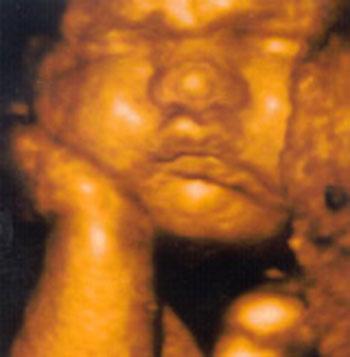

Ультразвуковые съёмки аборта на 12 неделе явно показывают: ребёнок чувствует боль, как любой из нас, и прекрасно понимает, что его хотят убить - он всеми силами старается отодвинуть от себя инструмент и широко раскрывает рот в безмолвном крике, когда у него отрывают сначала ноги, затем часть туловища…

Голову извлекают в последнюю очередь и лицо убитого ребёнка всегда искажено гримасой боли и ужаса. По этим кадрам видно, что практически нет разницы, убить ли 3-месячного ребёнка в утробе или отрезать руки -ноги -голову 5-летнему малышу. Без анестезии и в полном сознании.

- Фильм американского врача Бернарда Нэйтансона, названный «Безмолвный крик», показал всему миру, что такое аборт на сроке 11 недель беременности. Многие врачи и медсестры, посмотрев фильм, прекратили участвовать в абортах.

Это документальный фильм, и авторы рекомендуют соблюдать осторожность при его показе, поскольку некоторые кадры могут вызвать у человека психологический шок: безмолвный крик внутриутробного младенца, искаженное от боли лицо ребенка, погибающего на наших глазах...

Из закадрового текста к фильму: «Инструмент еще не коснулся ребенка, но он уже возбужден, его сердечные удары учащаются и достигают приблизительно 200 ударов в минуту. Вакуум-кюретка нащупывает ребенка, и он широко раскрывает рот в безмолвном крике».